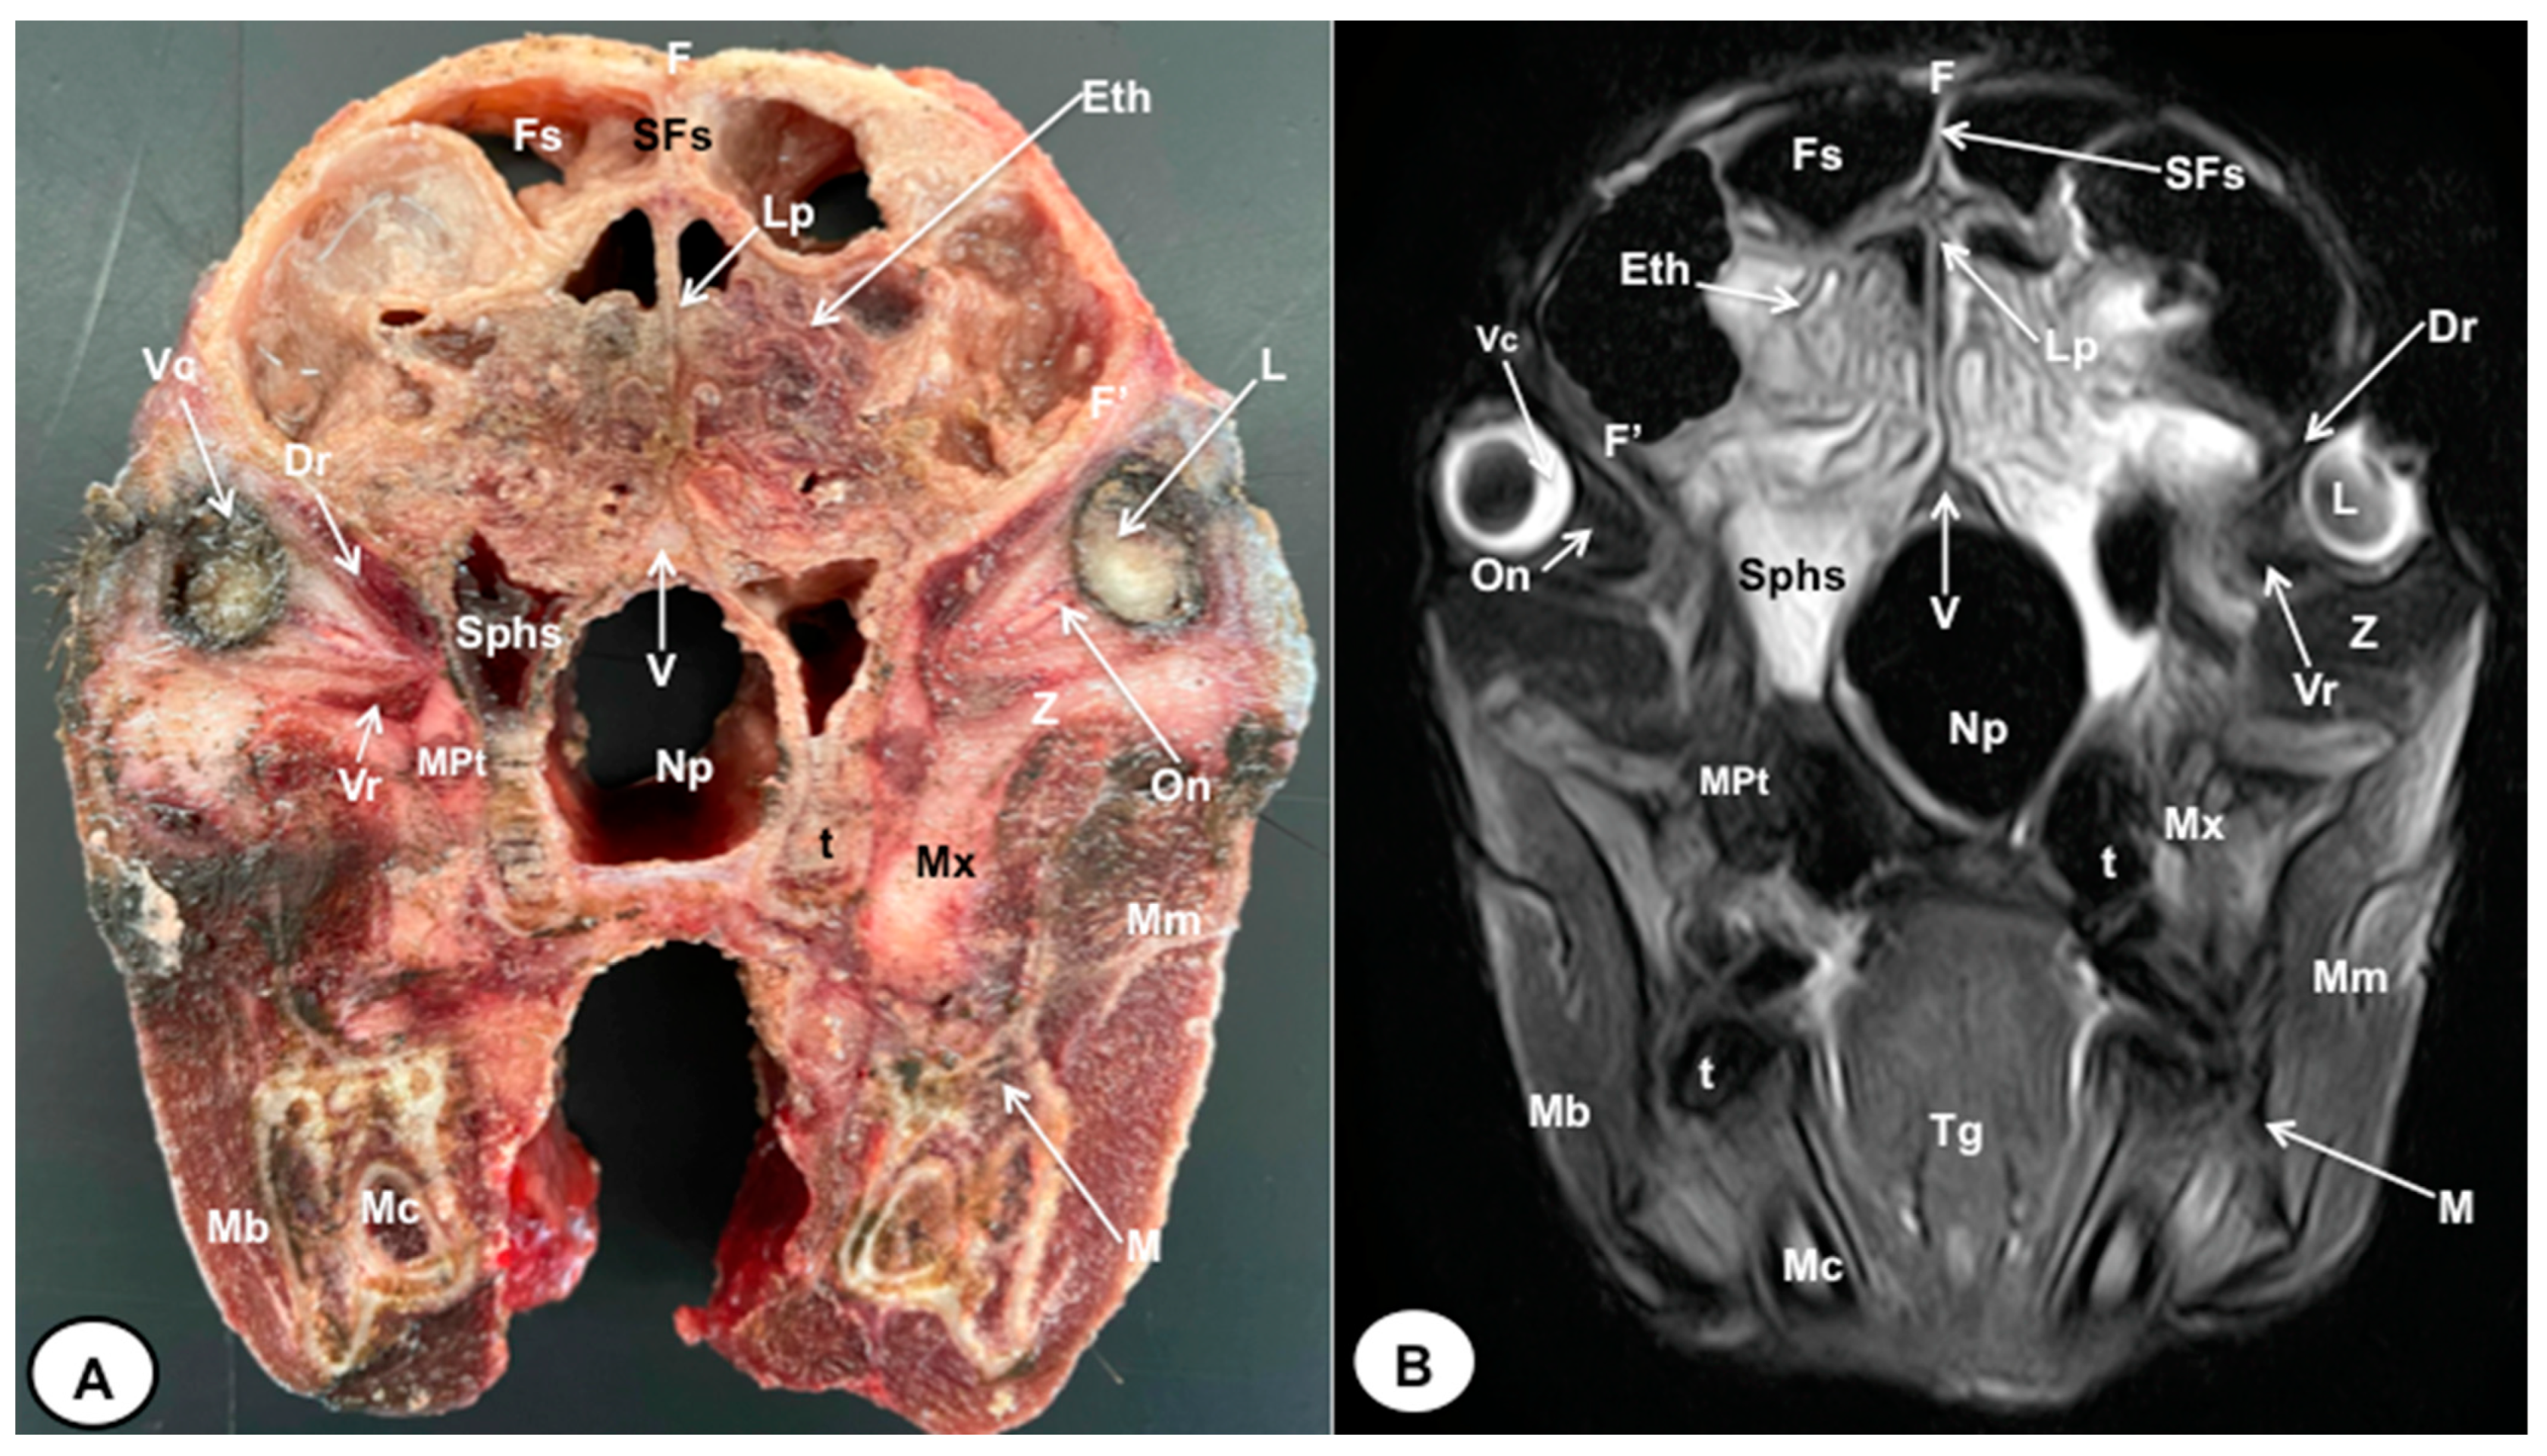

3.1. Anatomical Cross-Sections

3.2. Magnetic Resonance Imaging (MRI)